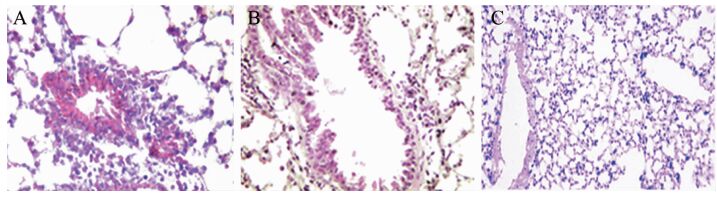

二、3组小鼠的肺组织病理检查结果对照组小鼠支气管黏膜下及管腔周围无炎性细胞浸润,管腔规则完整,肺泡结构完整清晰,基底膜无增厚、断裂情况,无新生血管形成。哮喘组小鼠支气管管腔狭窄,管壁增厚,黏膜充血、水肿,伴有炎症细胞浸润,基底膜增厚不规则,有新生血管形成。细辛脑组小鼠也有前述哮喘组的病理特点,但程度轻于较哮喘组,见图 1。

图 1 3组小鼠的肺组织病理检查结果(HE染色,×200) A:哮喘组;B:细辛脑组;C:对照组 |